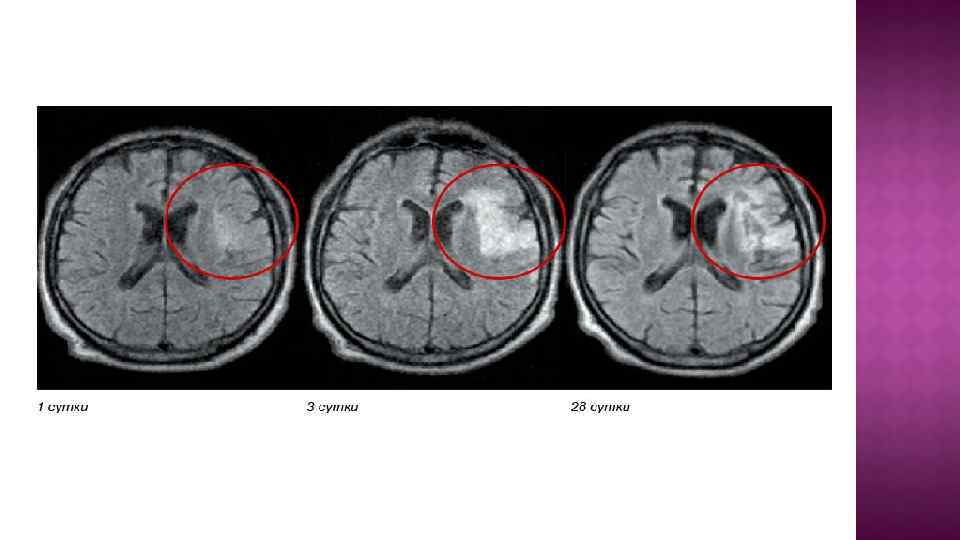

Тактика ведения больного с ТИА: Госпитализация. КТ / МРТ (> 1, 5 Т) во всех случаях. Заболевание сердца в анамнезе(да нет). Консультация кардиолога. Эхо КГ. ЭКГ. • формула крови • электролиты плазмы крови, креатинин. • Гематокрит , вязкость крови, протромбиновое время, осмолярность сыворотки, содержание фибриногена , агрегация тромбоцитов и эритроцитов, • Глюкоза крови. • Липиды крови. • Антифосфолипидные антитела.

Тактика ведения больного с ТИА: Госпитализация. КТ / МРТ (> 1, 5 Т) во всех случаях. Заболевание сердца в анамнезе(да нет). Консультация кардиолога. Эхо КГ. ЭКГ. • формула крови • электролиты плазмы крови, креатинин. • Гематокрит , вязкость крови, протромбиновое время, осмолярность сыворотки, содержание фибриногена , агрегация тромбоцитов и эритроцитов, • Глюкоза крови. • Липиды крови. • Антифосфолипидные антитела.